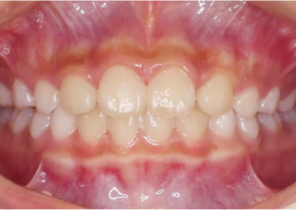

Case Report 2

7 years 11 months old, 24 stages of Invisalign® Palatal Expanders

Courtesy of Dr. David R. Boschken

Pre Invisalign Palatal Expander Expansion

Post Invisalign Palatal Expander Expansion

Post Invisalign Palatal Expander Treatment